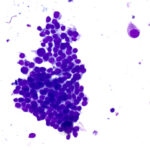

Consistent Results with ASP vial technology

Each FNA pass is placed into a propriety ASP vial and homogenized, ensuring the slide is always representative of the cell block. Control the volume of the sample for ROSE and preserve the rest for the cell block.